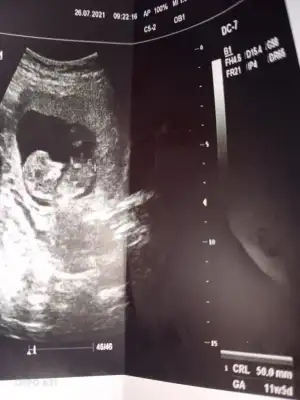

Kız gibi sanki emin olamadımEki Görüntüle 2892053 Eki Görüntüle 2892054 @Ikra meyra acaba müsait olunca bakar mısın? 11+6 oldu belli olur mu biraz?

Teşekkür ederimKız gibi sanki emin olamadım

Benim bebeğime de bakar mısınız 9 buçuk haftalık. Belki erken ama bir yorumunuz olursa diye merak ediyorumEn iyi 11 12 13 haftalar olmalışimdilik erkek yönünde ama yanıltabilir dediğim haftalar olmalı

Şimdilik erkek yönünde ama en iyi 11 12 13 haftalar olmalı tekrar USG paylasinBenim bebeğime de bakar mısınız 9 buçuk haftalık. Belki erken ama bir yorumunuz olursa diye merak ediyorum